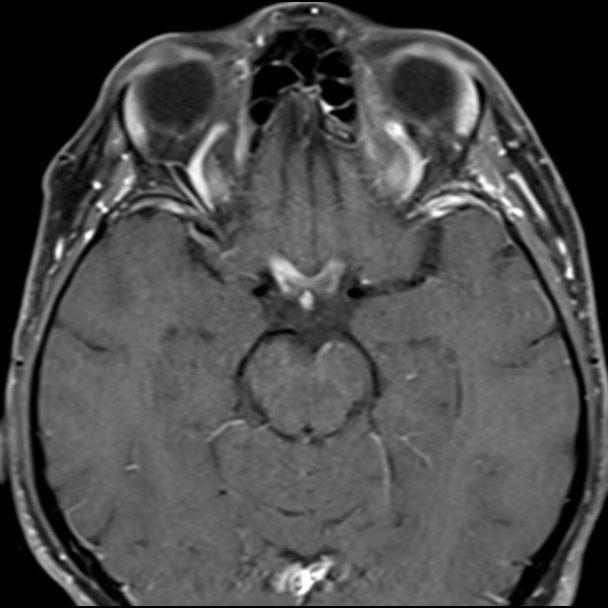

- (B) Orbita MRG’de aksiyel yağ baskılı T1A’da optik sinir prekiazmatik segmenti (oklar) gösterilmiş olup sırası ile aksiyel ve koronal post-kontrast yağ baskılı T1A görüntülerde bilateral optik sinir prekiazmatik segmentte kontrast tutulumu dikkati çekmektedir (oklar ve daire).